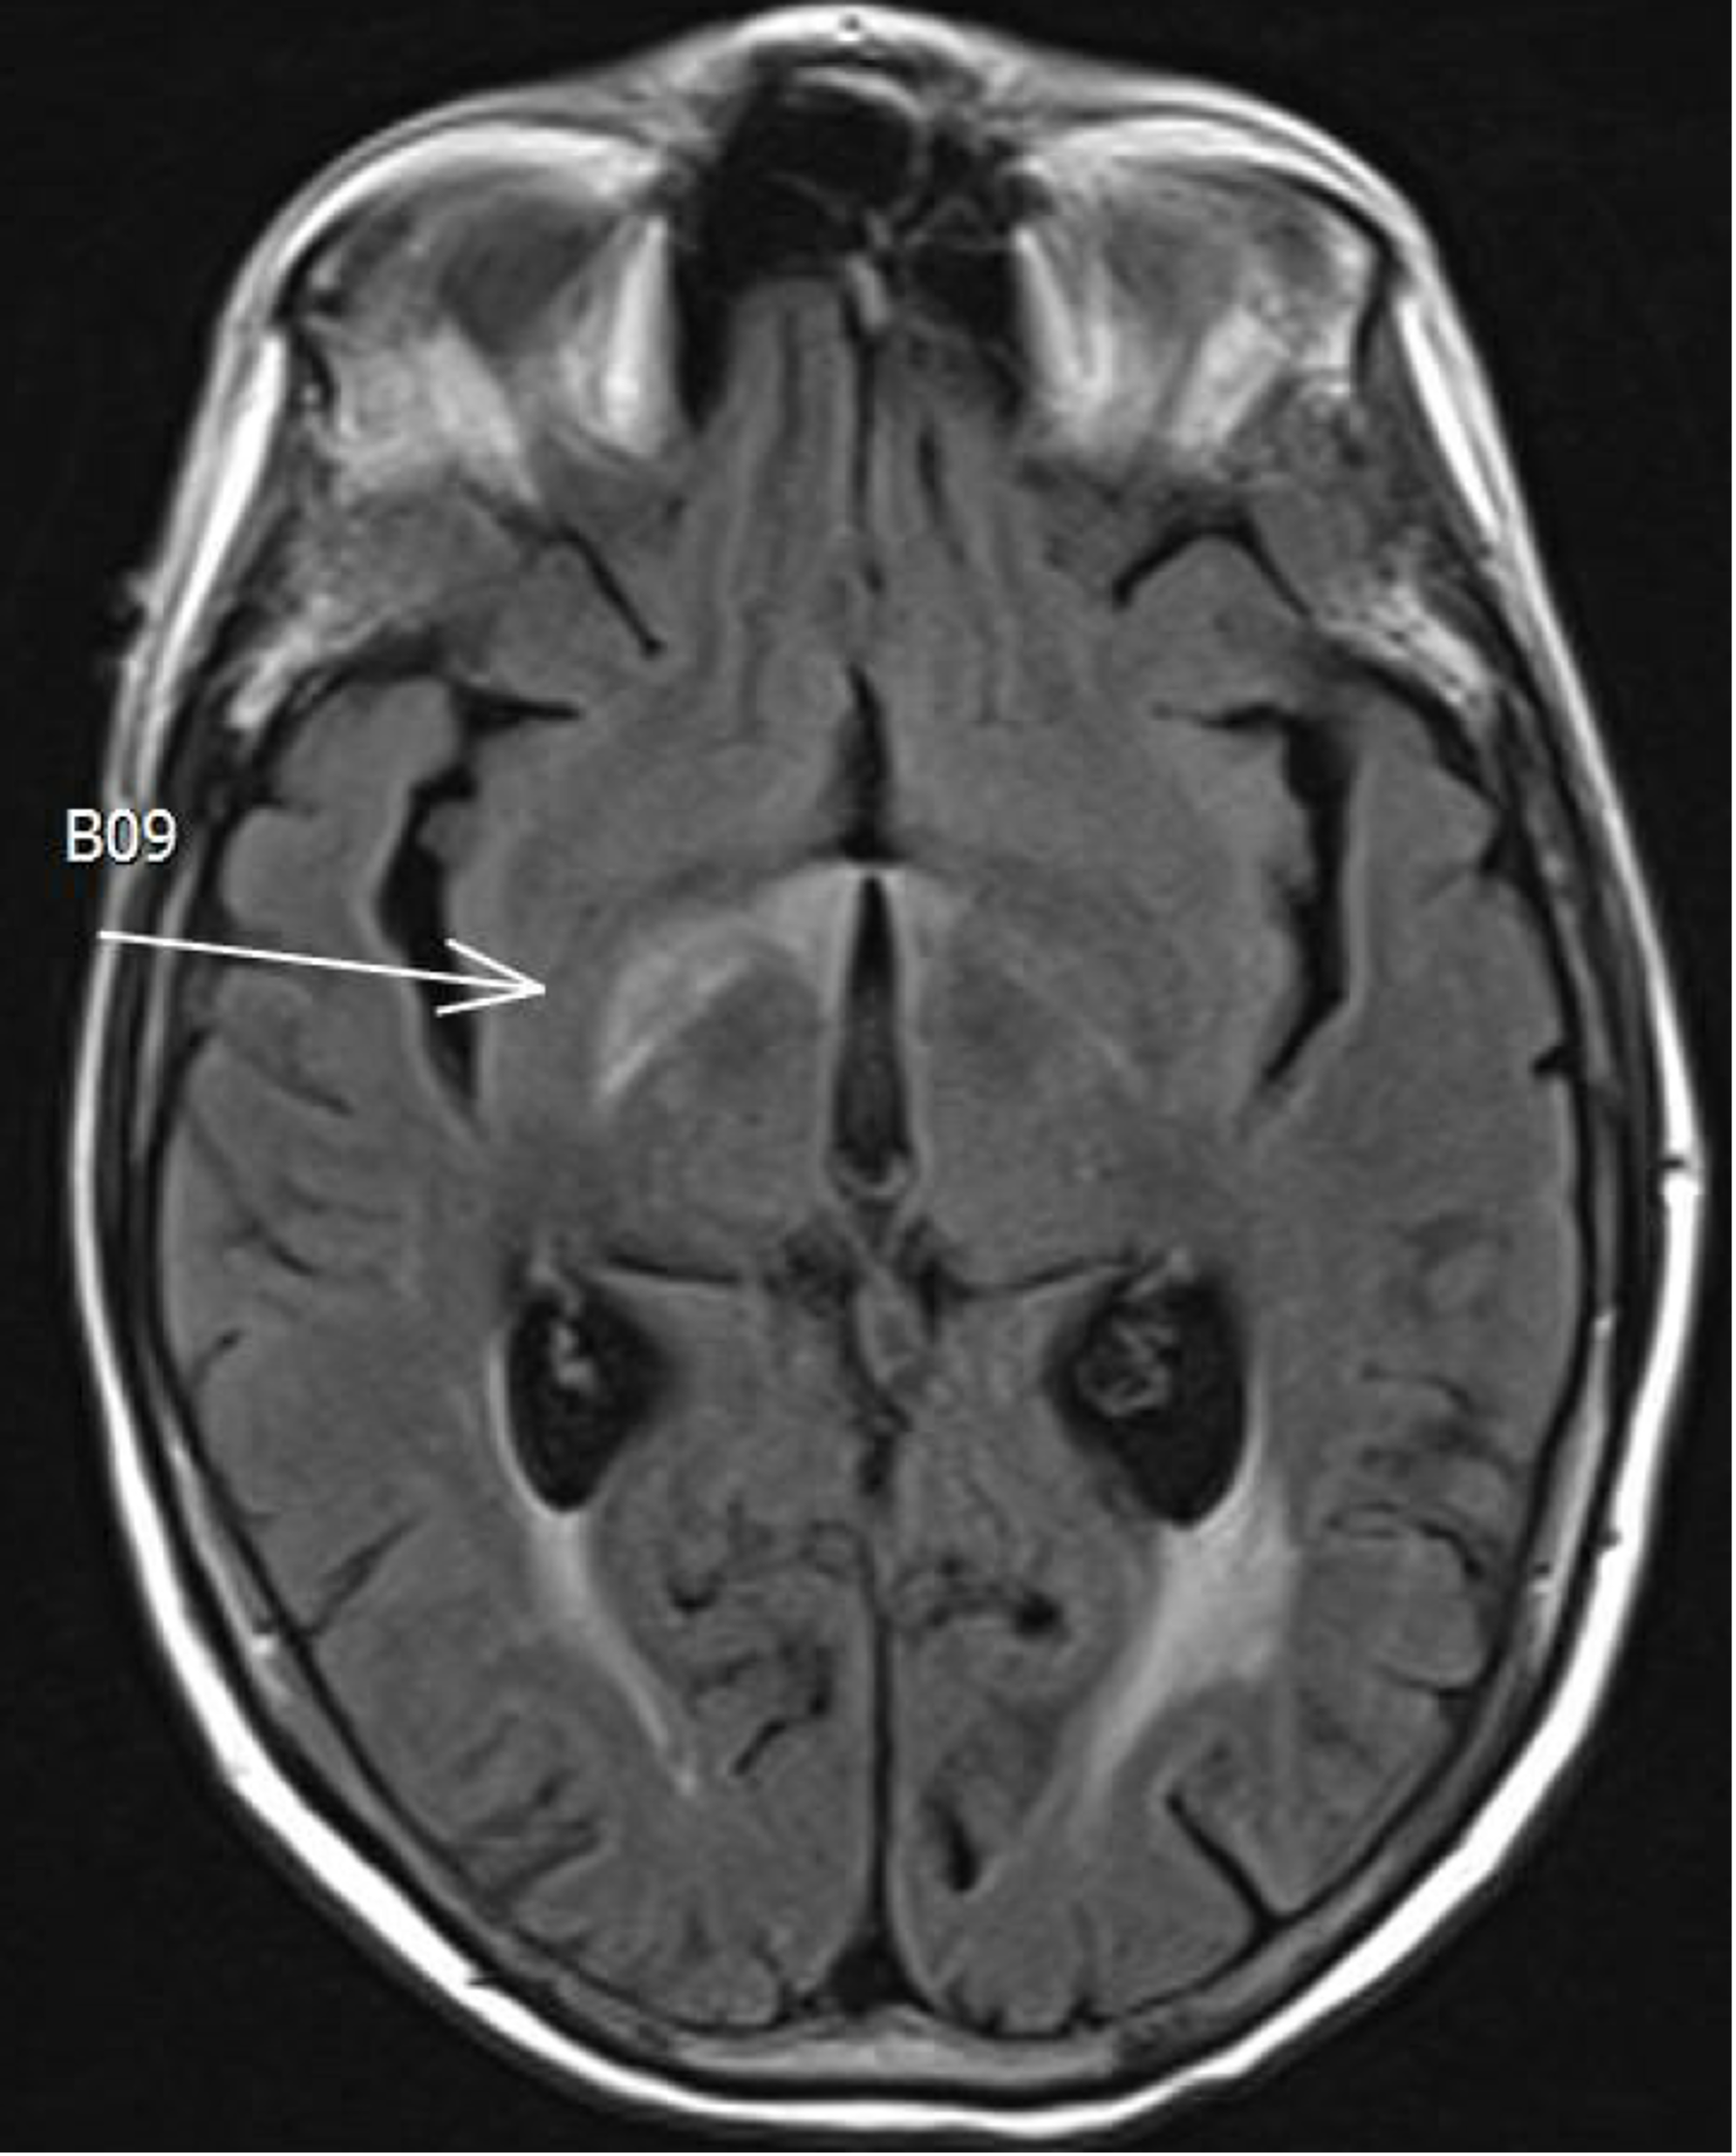

Figure 1. Axial post-gadolinium T1-weighted MRI (left) showed bilateral enhancement within the optic nerves anterior to the chiasm (arrows). Axial T2-FLAIR sequence showed an abnormality likely related to edema secondary to the enhancing foci (right). The findings were consistent with radiation optic neuropathy.

Testing/Laboratory work-up:

RION is a diagnosis of exclusion, with the most important condition to rule out being a recurrence of the previously treated tumor. MRI is the preferred imaging modality for diagnosis, since CT will often show no abnormalities in patients with RION. Typically for MRI, the unenhanced T1- and T2-weighted images show no abnormality, but the optic nerve will show post-gadolinium enhancement in T1-weighted images with MRI.(10, 17) The characteristic finding of RION is a discrete region of enhancement of the prechiasmatic optic nerve, often accompanied by expansion and T2 hyperintensity in the enhancing segment.(8) The enhancement of the optic nerve is believed to be due to radiation-induced disruption of the blood-brain barrier and accumulation of gadolinium within the nerve.(18) The exact pathogenesis of the optic nerve damage is unknown but microscopic investigation suggests the initial vascular injury results in perivascular inflammation, hyalinization and fibrosis of the vessel walls, loss of endothelium, and ensuing infarction with reactive gliosis.(18) These MRI imaging results can effectively rule out neoplastic infiltrative optic neuropathies since discrete areas of enhancement with expansion or T2 hyperintensity do not typically occur in these cases.(8)